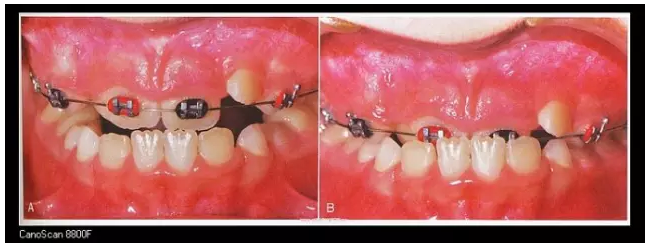

在部分患兒5-8歲左右,由于乳牙反咬合或者牙弓過窄等情況,可能經(jīng)過評估,醫(yī)生會建議使用預(yù)防矯治器或片段弓來解決。

三、擴(kuò)弓器

很多牙列不齊常伴隨牙弓過窄,所以擴(kuò)弓器是正畸醫(yī)生的好伙伴,它可以以多種形態(tài)和您見面。